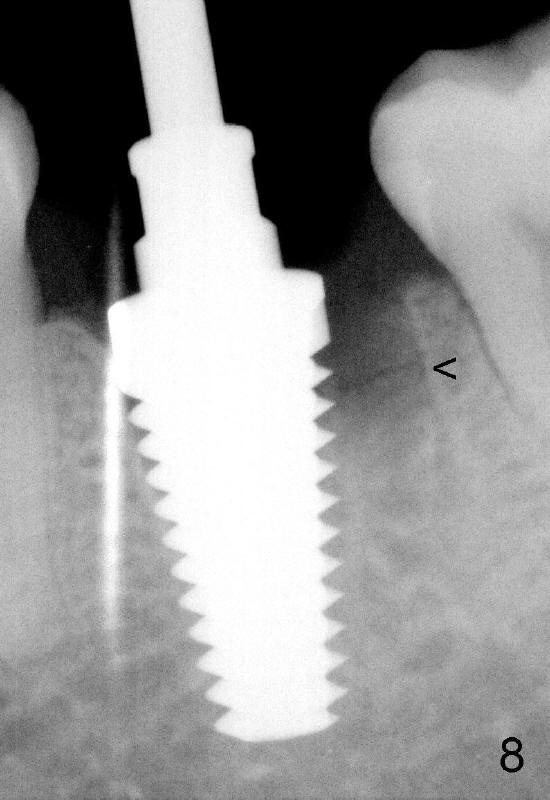

When 7x17 mm tap is placed, it drops mainly into the mesial socket (Fig.8). The septum appears to have been pushed to the distal one (<). When the 7x17 mm implant is placed with primary stability, the top portion is in the middle of the edentulous space (Fig.9). Sutures are placed mesial and distal to close the socket (Fig.10). The wound heals normally 3 months postop (Fig.11: ^). There is no bone resorption; the bone density on the top of the distal socket increases (Fig.12: D). The crown is fabricated 1 month later.